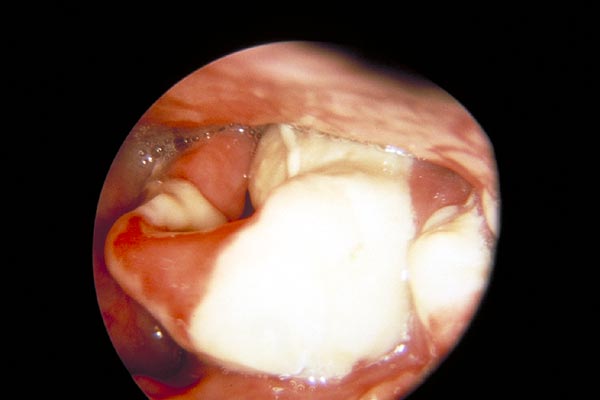

Stimmbandpolyp

|

Stimmbandkarzinom

laryngoskopieren